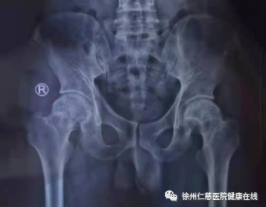

50岁男性患者,左股骨头无菌性坏死一年,综合评估后,采用髓芯减压植骨联合PRP加冲击波治疗,避免行髋关节置换术。

治疗前

髓芯减压植骨联合PRP加冲击波治疗

这种联合治疗针对病因,从根本上解决缺血原因。手术时间短、辐射少、创伤小、并发症少;手术不进入关节、术后对其功能影响小,恢复快。